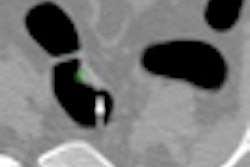

Patients with gunshot wounds are becoming increasingly common visitors in many emergency departments, especially those near large urban areas. These patients tend to have high mortality and morbidity rates, and injury assessment and evaluation of complications relies heavily on CT.

European Radiology has just published an important U.S. study involving 427 cases, and the article makes fascinating reading. The authors found that CT angiography can diagnose some unexpected injuries. To read more, visit our CT Digital Community, or click here.